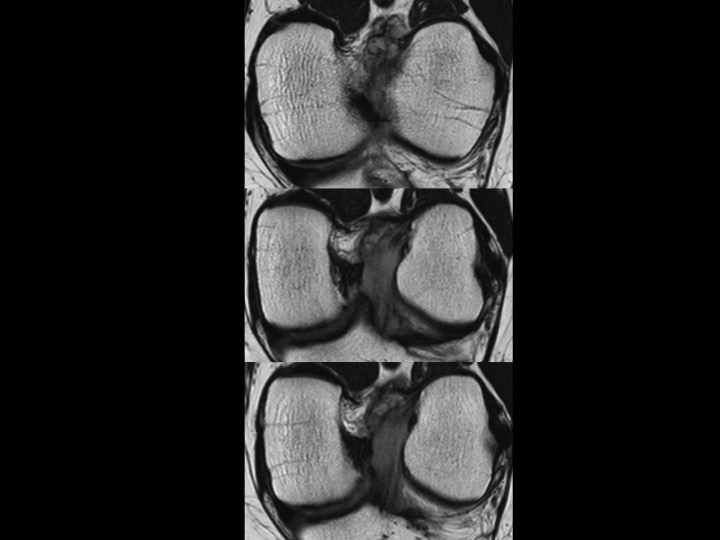

44M worsening knee pain

There is diffuse intrasubstance mucoid degeneration and expansion of the ACL with only small septated ACl ganglion near the femoral origin. This is typically seen in older individuals, but I like to think this gentleman is quite young. No other pathology on MRI. Apparently treatment is varied; Ive only found small series with good outcomes, but no mention of time to clinical follow up. It seems in this case that judicious debridement would be difficult, as the entire ligament seems to be rotten to the core. Reference article.

anterior cruciate ligament ( RID2781 )